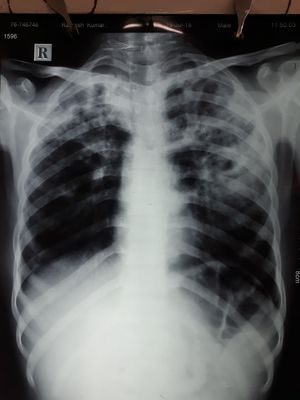

23 ur old male c/o cough with scanty sputum fever dyspnoea 2 month

Xray

Pulmonary koch's?

Beware of TB